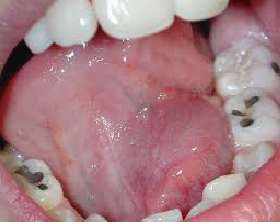

También llamada Medicina Bucal, es la rama de la odontología que se encarga del diagnóstico y manejo de las enfermedades propias de la boca y de las enfermedades sistémicas (de otros sitios del organismo), que tienen manifestaciones bucales.

El estomatólogo hace parte de un equipo de salud y está en la capacidad de diagnosticar patologías infecciosas, tumorales y de malformación, tomar biopsias y realizar tratamientos de urgencias, de síndromes dolorosos y disfunciones miofaciales y de la articulación temporo mandibular (ATM).